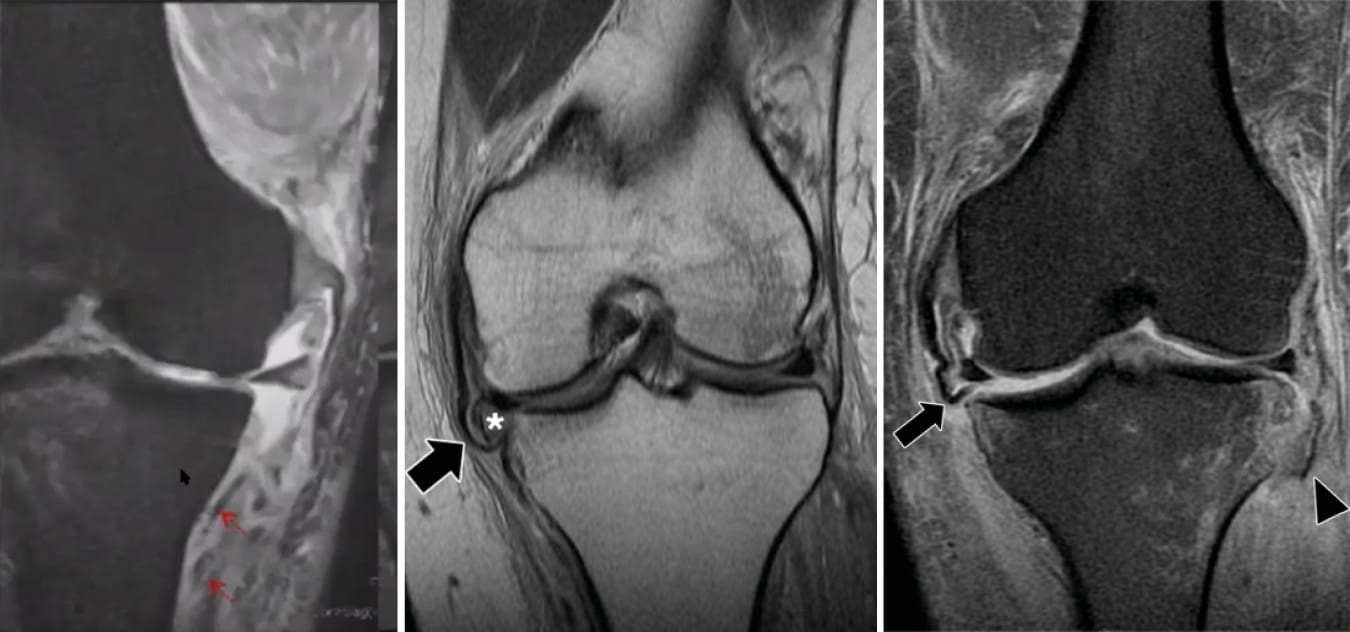

• MRI : Magnetic resonance imaging (MRI) is the gold standard examination for evaluating MCL and POL injuries. MRI is able to show the precise location of the injury, its severity and whether there is any other intra-articular damage (ACL, PCL, cartilage, menisci, subchondral bone or joint capsule).

Classification once again falls into three grades (Figure 10) but it differs from the AMA clinical classification. There is no real correlation between the two.

- Grade I: High signal intensity, oedema around the ligament

- Grade II: High signal intensity within the ligament, thickening, partial disruption of the fibres

- Grade III: Enthesis not visible, complete disruption, ligament appears distended, bony avulsion

On the axial images, the point of the posteromedial corner can be seen, including: POL, posteromedial joint capsule, posterior horn of medial meniscus, semimembranosus. If there is an injury, these structures will appear with low signal intensity on all sequences (Figure 11) [9] Fusco S, Albano D, Gitto S, Serpi F, Messina C, Sconfienza LM. Posteromedial Corner Injuries of the Knee: Imaging Findings. Semin Musculoskelet Radiol. juin 2024;28(3):318-26. .

Finally, MRI can be used to look for a Stener-like lesion, which is entrapment of MCL between the torn structures at the tibia, which can occur under the hamstrings, within the joint or under the medial meniscus (Figure 12).